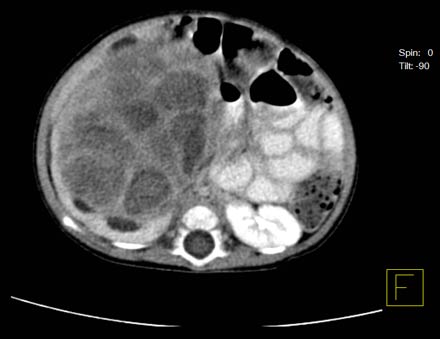

Un examen de exploración por TAC muestra un nefroma multilocular quístico (quiste de riñón) en un paciente pediátrico.

Nota: Las imágenes se muestra para fines ilustrativos. No trate de sacar conclusiones comparando esta imagen con otras en el sitio. Solamente los radiólogos calificados deben interpretar las imágenes.